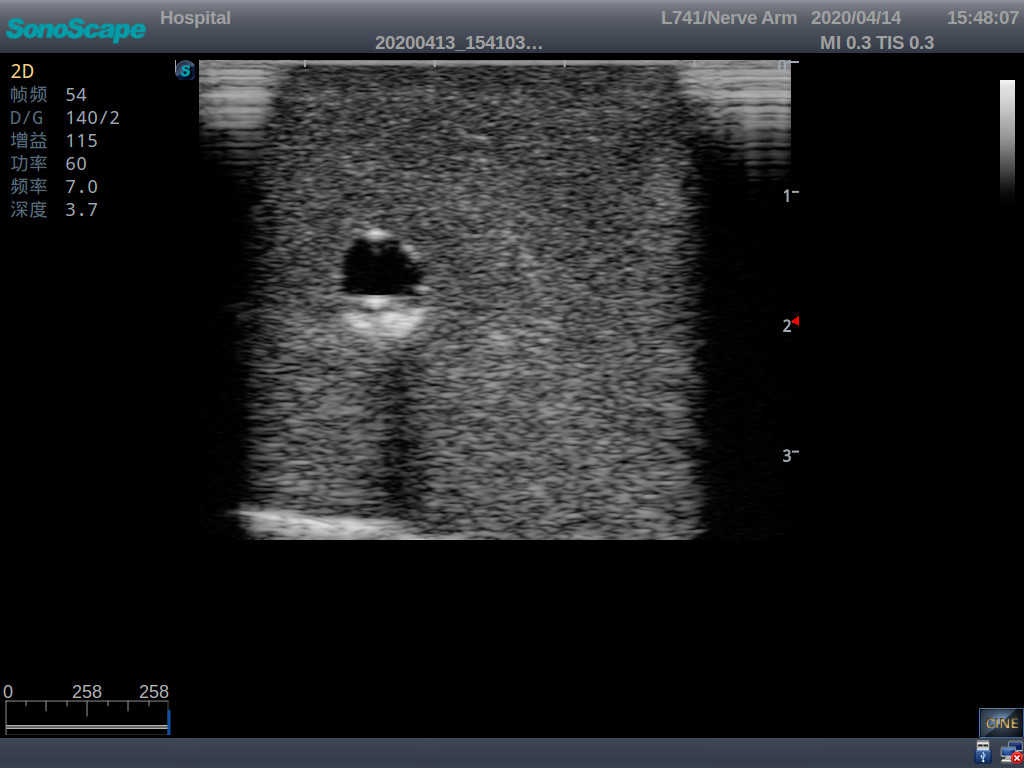

Product size(mm) 700×500×160

3)   Clear and real images of the tissues and organs (basilic vein and superior vena cava)